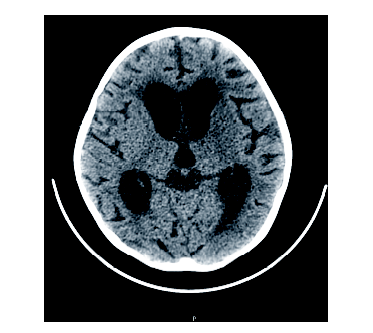

周正根(影像科主治医师):根据患儿的影像学图片介绍一下TBM的影像学特点, 首先, TBM比较容易出现脑积水, 见图1, 在脑底部的脑池可见分泌物, 脑室壁增厚; 其次, 脑室、脑沟可见到钙化, 见图2和图3, 钙化灶对结核的诊断有一定意义; 第三, 由于TBM可能侵犯到小血管, 所以可以见到一些低密度的梗塞病灶。

患儿确诊TBM, 治疗上继续三联抗结核治疗及鞘注抗结核药物。但后续治疗过程中患儿再次出现呕吐, 伴右侧肢体抖动、意识改变、双侧瞳孔不等大, 神志淡漠, 头颅CT平扫检查提示交通性脑积水, 双侧基底节区及左侧额叶、右侧顶叶皮层低密度灶, 考虑梗塞可能性大。遂予床边行颅骨钻孔脑室外引流术。并予甘露醇脱水减轻脑水肿。后患儿病情好转后转到胸科医院进一步专科抗结核治疗, 其间因脑积水在我院反复行左右脑室钻孔引流术, 最终行左侧脑室腹腔引流术。后患儿病情好转、稳定, 复查骨髓为完全缓解, MRD检测未见残留。遂按照GD2008广东协作组方案再次化疗, 并继续三联抗结核治疗, 其间多次查脑脊液TB-DNA定量水平均正常(10拷贝)。